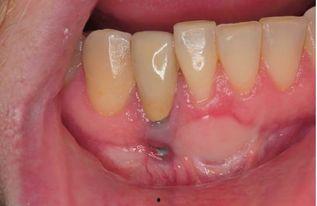

来看看这些失败的案例视频吧。视频中,一位患者痛苦地捂着嘴巴,种植牙已经松动,甚至部分脱落。另一位患者则因为种植牙感染,不得不进行二次手术。这些画面让人触目惊心,不禁让人质疑国产种植牙的质量。